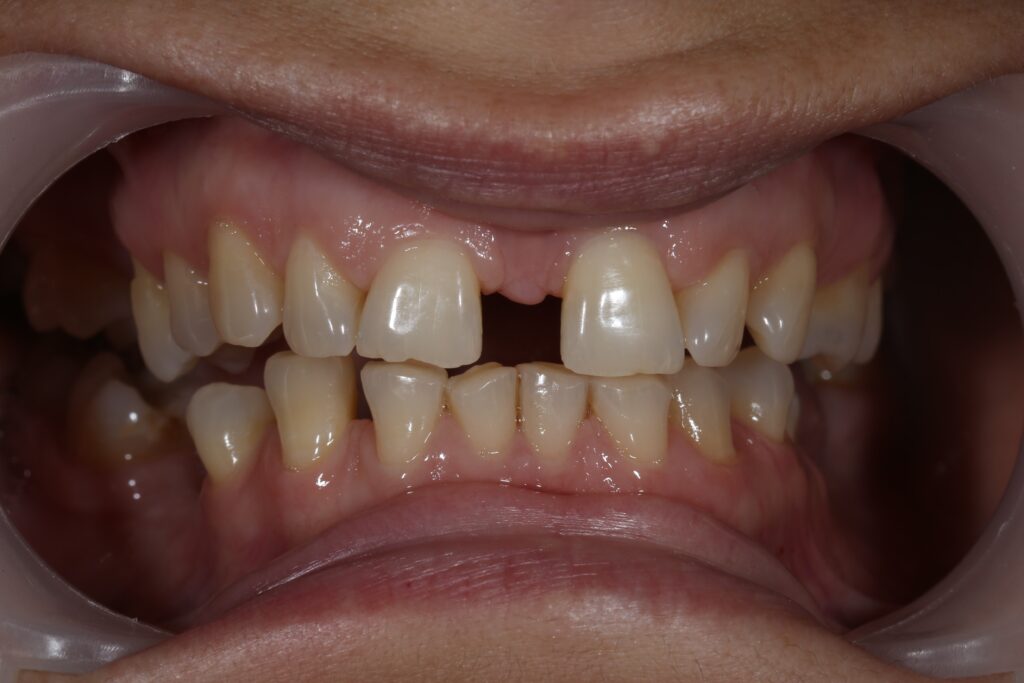

Ситуация до лечения

Пациент обратился за комплексным лечением.

Из-за множественных давних удалений жевательных зубов, произошла деформация зубных рядов, зубы разъехались в область удаленных, что затрудняло протезирование в момент обращения к ортопеду.

Так же можно отметить сильное снижение высоты прикуса (верхние зубы на 100% перекрывали нижние, что вызывало хроническую травму десны), а также повышенную стираемость твердых тканей зубов, что является следствием повышенной нагрузки, которую много лет испытывали передние зубы, в связи с отсутствием жевательных зубов.

В связи со всеми вышеперечисленными факторами, пациентка нуждалась в тотальной реабилитации.